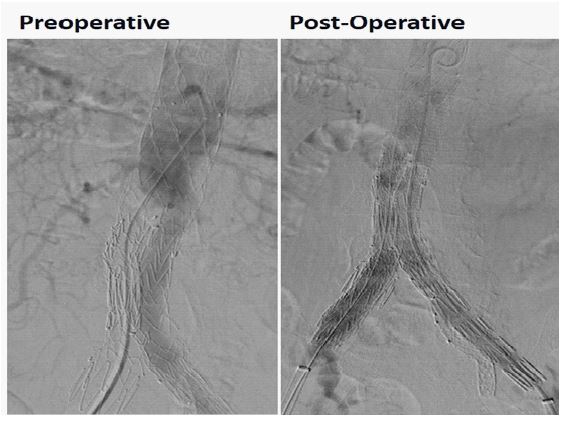

A male patient, 70 years, with hypertension and dyslipidemia, was admitted with an asymptomatic infrarenal abdominal aortic saccular aneurysm, measuring 3,6 cm. The patient was submitted to endovascular treatment with the aortic implant of endoprosthesis Jotec E-Tegra® 22×22×80 mm, followed by implant of Wrapsody 60×12×120 mm at left common iliac artery and Wrapsody 60×12×120 mm right common iliac artery, communicating with the aortic endoprosthesis. After that, it was performed a kissing balloon at both common iliac arteries with a catheter balloon 10x60 mm. The final image showed excellent results with no endoleaks. (Figure 1). The patient was discharged from the hospital on the first day post-operative and 1-month follow-up showed endoprosthesis patency with no endoleaks.

Figure 1: Aortic implant of endoprosthesis Jotec E-Tegra® 22×22×80 mm, followed by implant of Wrapsody 60×12×120 mm at left common iliac artery and Wrapsody 60×12×120 mm right common iliac artery, communicating with the aortic endoprosthesis.